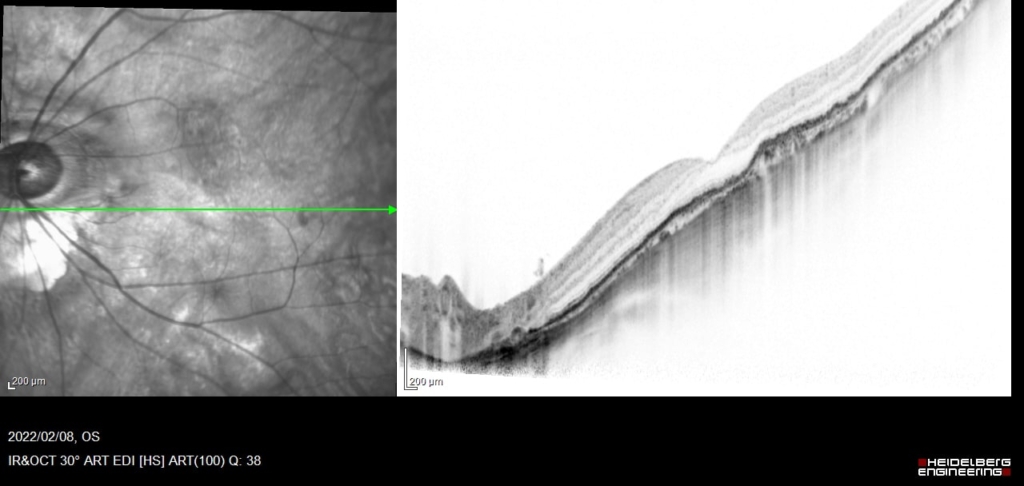

5wで硝子体注射

CNVの活動性の指標として、PED内部のCNVとBruch膜に間にBruch膜を後方に押すように生じる間隙や、PED自体の増大は注意が必要。